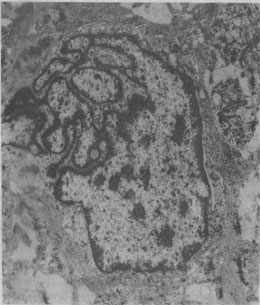

图1-1 恶性肿瘤细胞的奇异形核

图中央为一巨大的瘤细胞核,核膜曲折凹陷,使核呈奇异形(纤维肉瘤的电镜照片)×23000